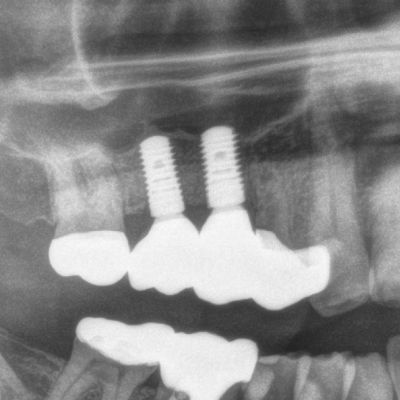

Sinuslift mit Eigenknochen und späterer Implantation

Implantation & Sinuslift (Aufbau des Kieferknochens in der Kieferhöhle)

Implantatgetragene Kronen